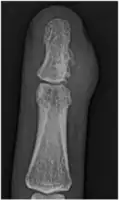

A well-defined area of bone loss in the medulla of the bone is seen on x-ray.[2]

- X-Ray right middle finger: juxta-cortical chondroma